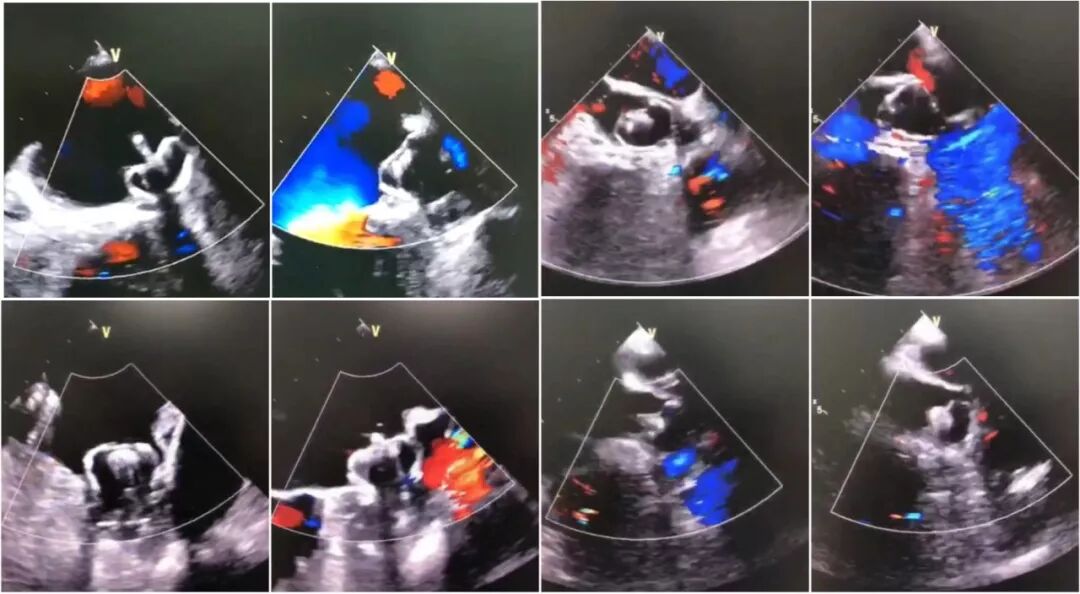

胸科左心耳封堵团队当日八例精彩Watchman左心耳封堵术:

8例左心耳封堵术

8例左心耳封堵术TEE标准化评价